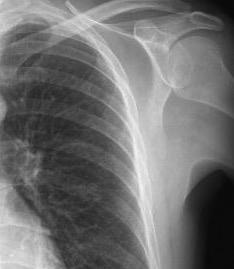

Hallazgo temprano: Osteopenia general. Erosión marginal del borde inferior de la cabeza humeral.

Osteólisis del extremo externo de la clavícula.

Cuomo F et al. THE RHEUMATOID SHOULDER.